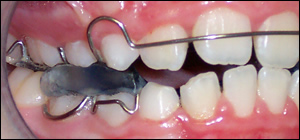

Fig 2: Twin Block appliances were fabricated to open the bite and advance the mandible.